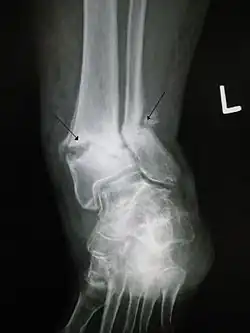

Open ankle fracture with luxation

In orthopedic medicine, fractures are classified in various ways. Historically, they are named after the physician who first described the fracture conditions; however, there are more systematic classifications as well.

They may be divided into stable versus unstable depending on the likelihood that they may shift further.